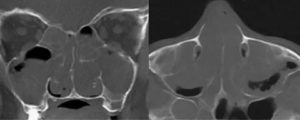

КТ пазух носа или компьютерная томография — неинвазивное информативное исследование, которое позволяет определить состояние тканей послойно.

КТ помогает врачу оценить:

- контуры,

- структуру,

- объём,

- минерализацию и плотность новообразований.

Исследование неоценимо при определении эффективности медикаментозной терапии на фоне хронических заболеваний носа.

Единственный недостаток метода — дороговизна. Альтернативной компьютерной томографии является процедура МРТ.